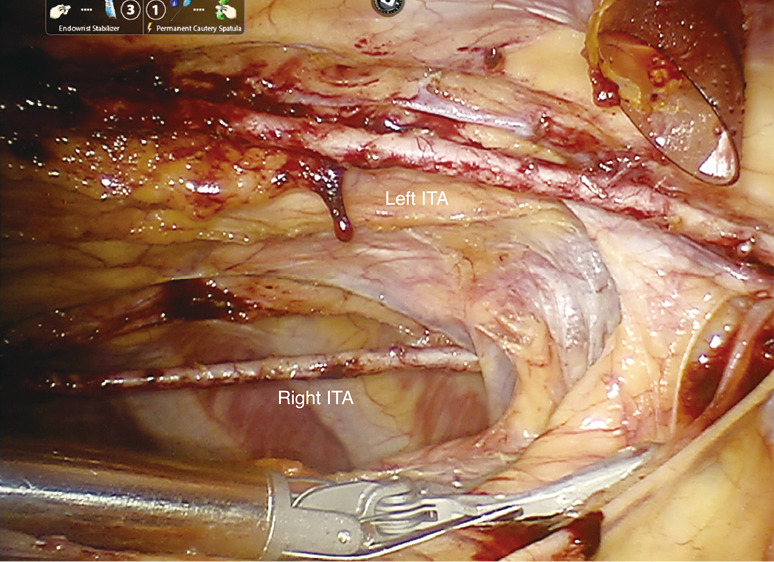

Methods: A total of 871 patients underwent robotic TECAB at our institution from 7/2013 to 4/2024. Of these, 406 patients received BITA grafts and are the subject of this review. Early and mid-term clinical outcomes were reviewed and angiographic patency in those undergoing hybrid revascularization with percutaneous coronary intervention (PCI) after TECAB. All cases were performed via a beating-heart robotic approach, with standard TECAB port placement.

Conclusions: Use of the beating-heart robotic TECAB approach facilitates BITA grafting to achieve multi-vessel arterial revascularization of the left coronary system, with excellent 10-year outcomes.